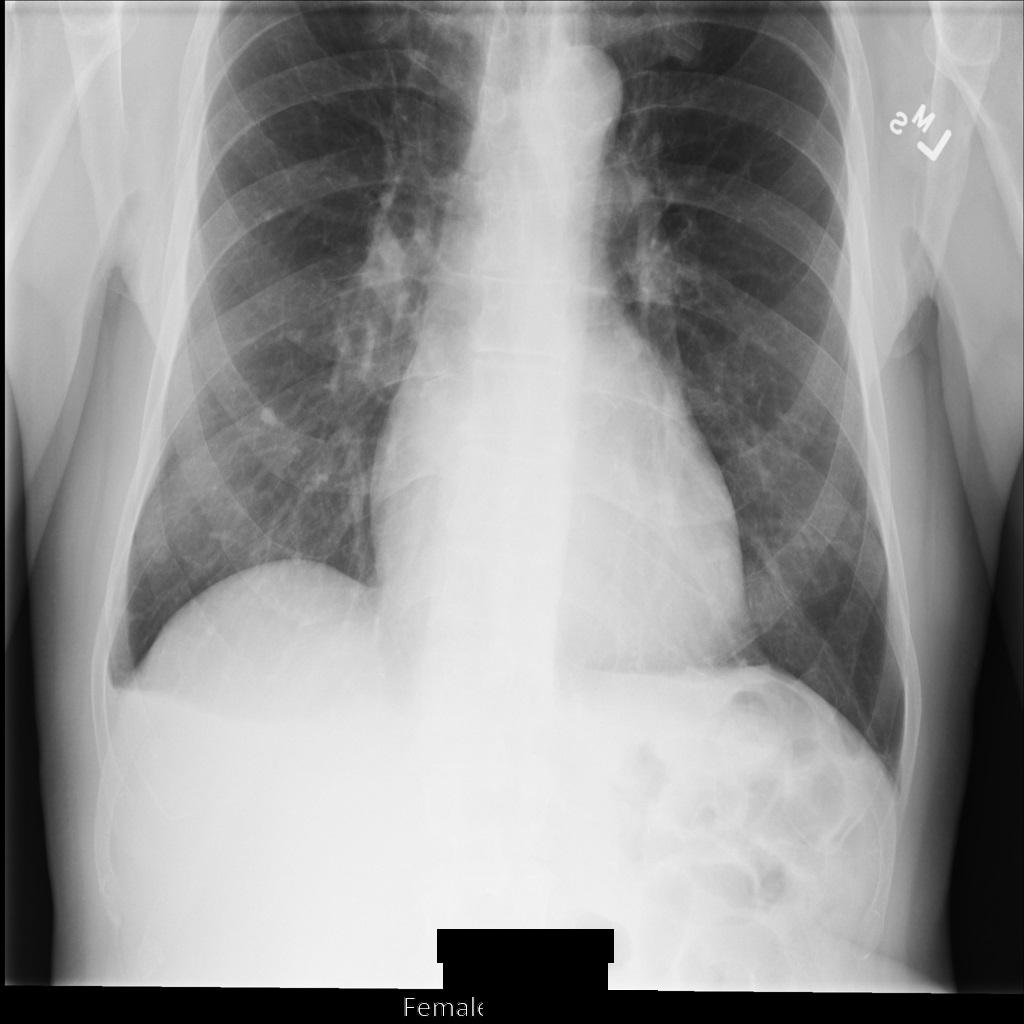

Depois de remover a identificação da imagem com REDACT_ALL_TEXT

, a imagem

tem o seguinte aspeto. Repare que todo o texto incorporado na parte inferior da imagem foi ocultado.

REDACT_ALL_TEXT